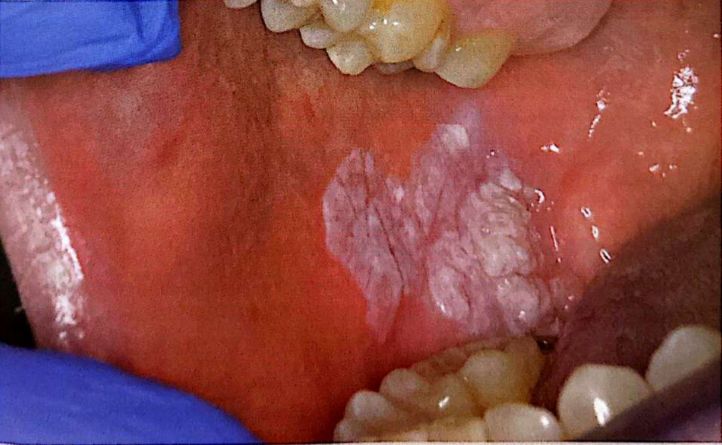

CASO CLÍNICO 1: PATOLOGÍA ORAL GERIÁTRICA

Paciente: Varón de 78 años, antiguo agricultor. Historia: Consumidor habitual de tabaco de mascar. Nota una "masa" de crecimiento lento sin dolor agudo. Exploración: Placa blanquecina extensa, gruesa, exofítica y verrugosa en fondo de vestíbulo inferior derecho. Firme a la palpación, no indurada. Sin adenopatías.

1. Basándose en la clínica y la epidemiología descrita, su sospecha diagnóstica principal es un Carcinoma Verrucoso de Ackerman. Respecto a la etiología y asociaciones de esta entidad, señale la afirmación correcta: